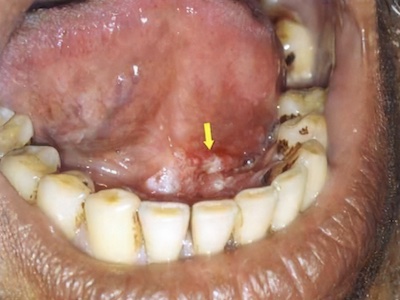

口底癌是指原发于口底黏膜的癌,居口腔及唇癌的第六位。一般在两侧前磨牙以前称为前口底,在其后称为后口底。多数口底癌为中度分化的鳞癌,极少数为来自口底小唾液腺的腺上皮癌。口底癌的发生与白斑、扁平苔癣等癌前病变的存在,以及烟、酒嗜好等因素有关。

口底癌的发病年龄为40-60岁,多见于舌系带两侧的前口底,局部可出现溃疡或肿块。由于口底区域不大,肿瘤易侵犯舌系带而至对侧,并很快向前侵及牙龈和下颌骨舌侧骨板、骨松质,使下前牙松动,甚至脱落。

发生于后口底者,其恶性程度较前部为高,且易早期侵犯舌腹及下颌骨。晚期肿瘤可侵及牙龈、下颌骨、舌体、咽前柱、舌下腺、下颌下腺导管、下颌下腺及口底肌群。肿瘤侵犯舌体可导致舌运动障碍,固定于口内。